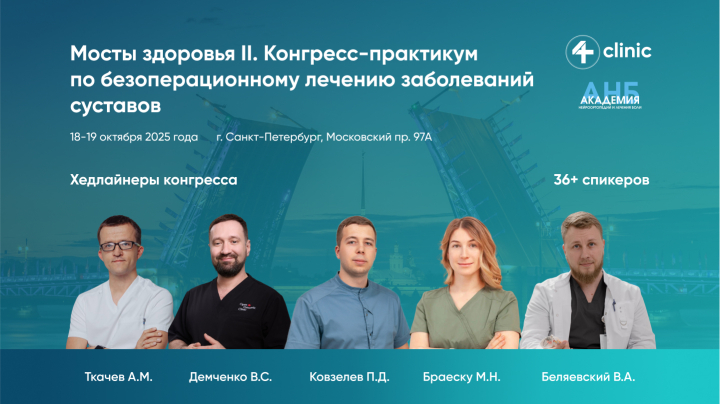

Мосты здоровья II. Конгресс-практикум по безоперац...

Уважаемые коллеги! Приглашаем вас принять участие в конгрессе-практикуме по безоперационному лечению заболеваний суставов «Мосты...

1080 мин